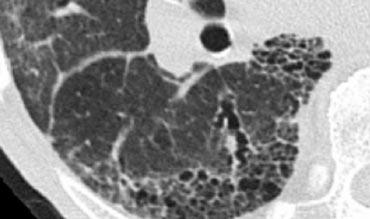

Honeycombing

Tổ ong được định nghĩa bởi sự hiện diện của các khoang nang nhỏ với thành dày không đều được cấu tạo bởi mô xơ.

Các nang tổ ong thường chiếm ưu thế ở vùng phổi ngoại vi và dưới màng phổi bất kể nguyên nhân của chúng.

Các nang tổ ong dưới màng phổi thường xuất hiện theo nhiều lớp liên tiếp.

Đặc điểm này có thể giúp phân biệt tổ ong với khí phế thũng cạnh vách ngăn, trong đó các nang dưới màng phổi thường chỉ xuất hiện theo một lớp duy nhất.

Trường hợp bên trái cho thấy các nang tổ ong dưới màng phổi ở nhiều lớp liên tiếp.

Ngoài ra còn có sự chiếm ưu thế ở thùy dưới và giãn phế quản do co kéo lan rộng.

Những phát hiện này điển hình cho Viêm phổi Mô kẽ Thông thường (UIP).

UIP hay ‘phổi giai đoạn cuối’ là một chẩn đoán bệnh lý và thường được xác định qua sinh thiết phổi, khi hình ảnh tổ ong có thể nhìn thấy được.

Xơ phổi vô căn (IPF) chiếm hơn 60% các trường hợp UIP.

UIP kèm xơ hóa phổi cũng là một dạng tổn thương phổ biến trong bệnh tự miễn và tổn thương phổi do thuốc.